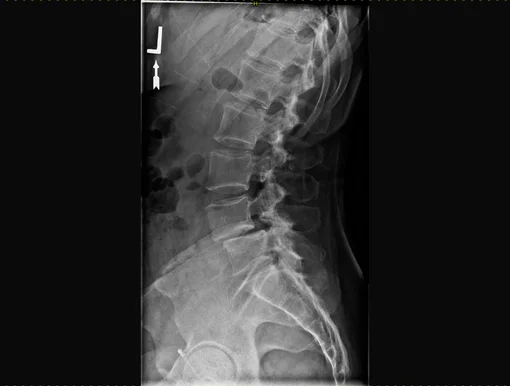

According to biological aging, degeneration runs in different phases. Initially, the water retention capacity decreases, resulting in a possible painful segmental hypermobility. During this phase, diagnostic imaging is often inconclusive. X-rays can show retrolisthesis, a reverse sliding of the upper vertebra over the lower vertebra. In the MRI, the affected intervertebral disc appears plain black (black disc), sometimes a small collection of fluid is seen in the rear fiber ring (annular tear), which is accepted as apparent pain symptom.

During the further course of the process, substance of the intervertebral disc is decreasing, disc height is diminished, leading, regardless of protrusions and/or herniations, to narrowing of the nerve exits, a lateral narrowing of the spinal canal called lateral stenosis. Advanced stages of degeneration lead to a complete loss of disc height causing complete narrowing of the spinal canal (central stenosis). X-rays and MRI show typical signs as well. Although increased stiffening can be assumed in the advanced stages, segmental instabilities can regularly be found, causing pain.

Sliding of the vertebral body (spondylolisthesis) can be divided into different groups. The most common causes are congenital or acquired conditions and generally occur in younger patients. However, with increasing age, the degenerative form of spondylolisthesis also plays a role. The main result is always instability with relating symptoms and the development of spinal stenosis. Decisive for this type of instability is that it is always characterized by a forward sliding of the upper vertebra against the lower vertebra.